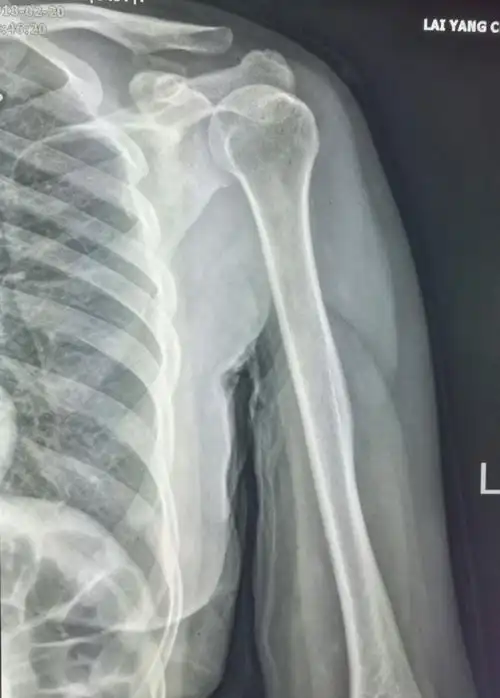

写美篇这个病例提醒我们,肩部背部外伤要注意肩胛骨,肩关节正位不宜